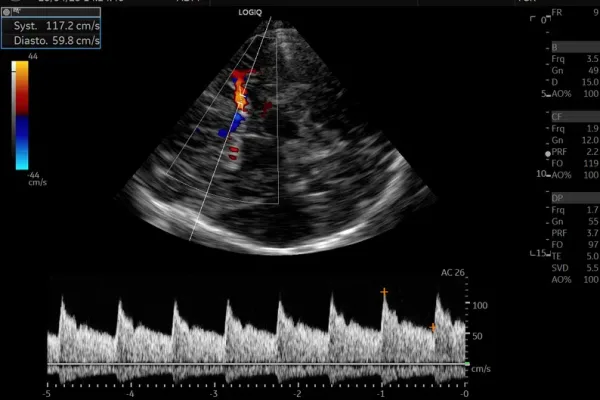

Notre service d’Imagerie Médicale et Radiologie Interventionnelle, un pilier essentiel de notre approche diagnostique. Avec une expertise avancée et une technologie de pointe, nous offrons une imagerie de haute précision pour éclairer votre parcours médical. Notre équipe de spécialistes dévoués s’engage à fournir des diagnostics fiables et des soins personnalisés, en mettant l’accent sur votre bien-être et votre satisfaction. Vous pouvez compter sur nous pour une expérience professionnelle et des résultats médicaux de qualité supérieure.

Échographie GE LOGIQ S8